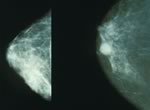

11 мая в Алуште состоялась конференция, посвященная таргетной терапии солидных опухолей, в частности лечению рака молочной железы, который на сегодня является значимой причиной смерти женщин во всем мире.